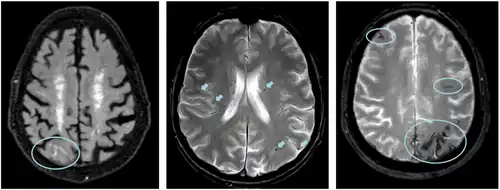

MRI scans of the human brain, examples of ARIA highlighted in blue:

Left: ARIA-E with sulcal effusion (FLAIR sequence)

Middle: ARIA-H with multiple microbleeds (T2* weighted)

Right: ARIA-H with superficial siderosis (T2* weighted)